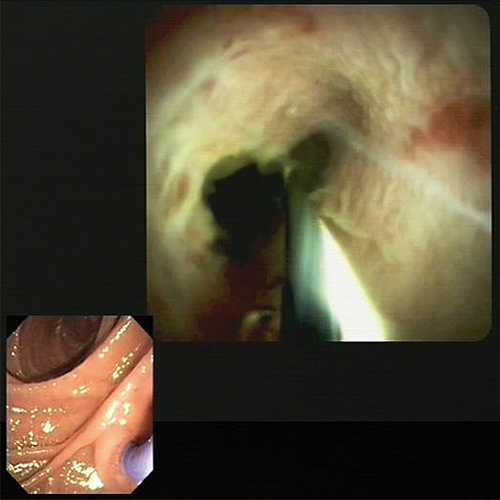

- Innere Medizin, Gastroenterologie